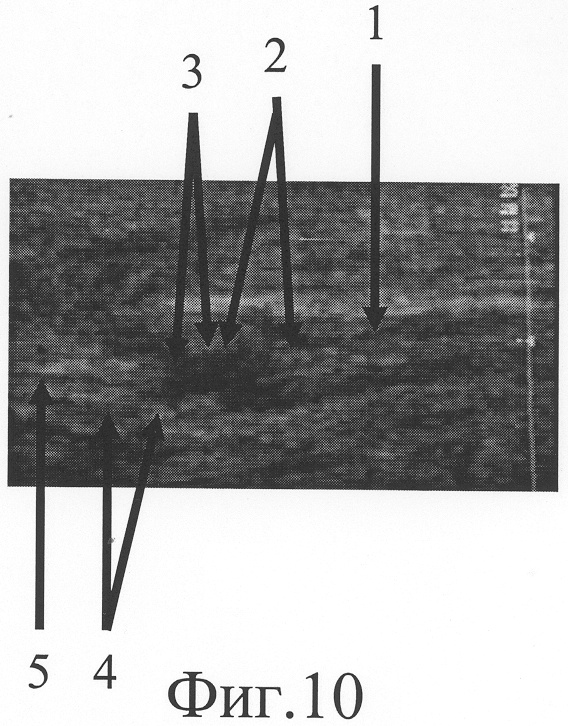

На фиг.5 представлена сонограмма больного Л., 23 лет, с застарелым повреждением локтевого нерва на границе средней и нижней трети правого предплечья.

При ультрасонографическом исследовании (фиг.5) установлено, что проксимальный фрагмент локтевого нерва (фиг.5-1) прерывается в средней трети предплечья, на его конце располагается неврома, линейный размер которой составляет 10 мм (фиг.5-2). Дистальный фрагмент нерва, обнаруженный на границе средней и нижней трети предплечья (фиг.5-5), патологически измененен на протяжении 6 мм (фиг.5-4). Диастаз между невромой и дистальным фрагментом равен 21 мм (фиг.5-3). Размер участка срединного нерва, подлежащего возмещению, составляет сумму линейного размера невромы проксимального фрагмента по линии продольной оси нервного ствола, протяженности диастаза между невромой и дистальным фрагментом, линейного размера патологически изменененного дистального фрагмента и равен 37 мм.